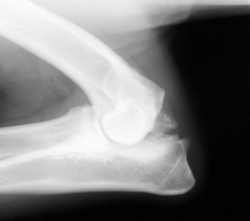

L’arthrose chez le chien et le chat

L’arthrose est une affection des articulations

Cette affection correspond à une “usure” des cartilages avec des modifications et des irrégularités des os sous-jacents.